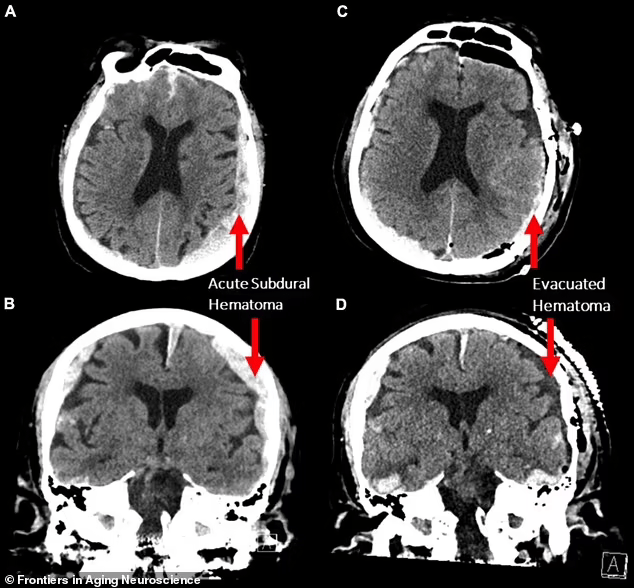

Theo một bài báo đăng trên tạp chí Frontiers in Aging Neuroscience , bệnh viện Đa khoa Vancouver ở British Columbia đã tiếp nhận một người đàn ông 87 tuổi bị co giật và ngừng tim. Một hoạt động não sắp chết đã vô tình được ghi lại khi các nhà khoa học thần kinh sử dụng phương pháp ghi điện não đồ (EEG) để phát hiện và điều trị nó.

Tiến sĩ Ajmal Zemmar của Đại học Louisville, Kentucky, Hoa Kỳ, đã tham gia vào cuộc nghiên cứu. Ông cho biết nhóm nghiên cứu đã đo hoạt động của não trong 900 giây trước và sau khi chết và đặt trọng tâm vào nghiên cứu những gì xảy ra trong 30 giây trước và sau khi tim ngừng đập.